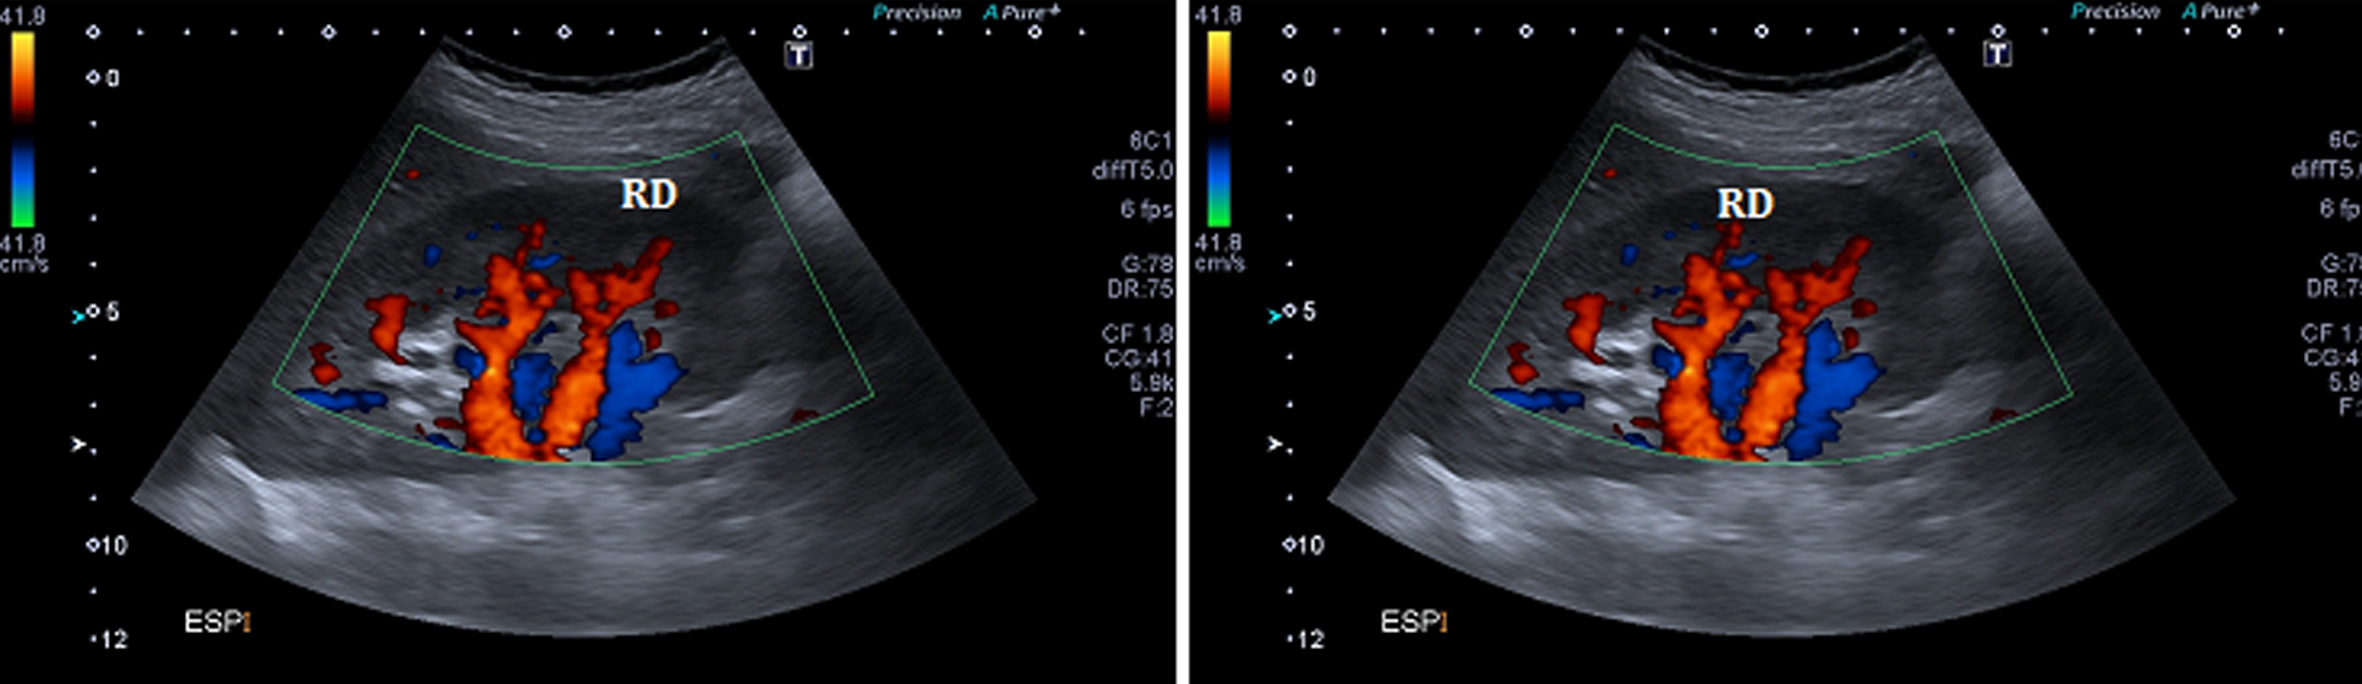

Posteriormente se realiza ecografía Doppler color de las arterias renales a efectos de valorar el patrón hemodinámico en las mismas, particularmente en la arteria renal derecha, y evidenciar en tiempo real cambios en dicho patrón vinculados a la fase del ciclo respiratorio (estudio dinámico).

Se comprueba una aorta abdominal ectásica en toda su extensión, con velocidades sisto-diastólicas habituales (velocidad picosistólica de 70 cm/seg.). Ambos riñones son de forma y tamaño habitual, con parénquima de espesor y ecogenicidad normal y buena diferenciación córtico-medular bilateralmente. No se ven alteraciones de las cavidades excretoras. Se realiza estudio dinámico de las arterias renales durante el ciclo respiratorio el cual demuestra que durante la inspiración el sector proximal de la arteria renal derecha se “verticaliza”, quedando paralela a la aorta abdominal, (Fig. 5), comprobándose además aumento de las velocidades sisto-diastólicas en este sector de la arteria, con velocidades picosistólicas (VPS) de 385 cm/seg en inspiración, comportándose desde el punto de vista hemodinámico como una estenosis significativa.

En esta fase del ciclo se observa íntimo contacto entre el sector proximal de la arteria renal derecha y la crura diafragmática ipsilateral, en concordancia con lo visto por angioTC.

Durante la inspiración es también evidente una disminución significativa de la vascularización del riñón derecho, con ondas de flujo de tipo “tardus et parvus” a nivel intrarrenal compatible con flujo post-obstructivo (postestenótico). (Fig. 6)

En espiración la arteria tiene un trayecto horizontal y velocidades de flujo normales (VPS de 122 cm/seg) (Fig. 5), siendo la vascularización intrarrenal de distribución habitual y con patrones de flujo normales. (Fig. 4)

Figura 4

Ecografía Doppler, Cortes longitudinales. En espiración (izquierda) y en inspiración (derecha). (RD) Riñón derecho.